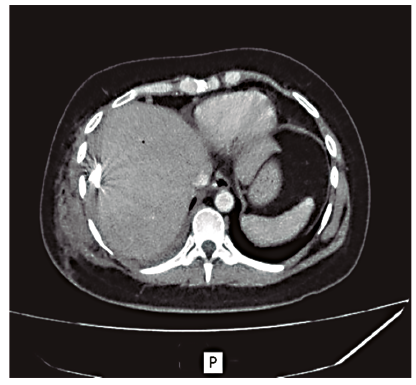

Con este hallazgo se decidió realizar el drenaje percutáneo de dicha colección bajo guía ecográfica, con la colocación de un catéter multipropósito de 12 Fr, lográndose evacuar 400 ml de líquido hematopurulento, cuyo cultivo fue positivo para Escherichia coli sensible. A las 24 horas, debido a que la paciente continuaba con sintomatología respiratoria, se realizó una nueva TC que evidenció una disminución marcada del componente líquido de la colección, persistencia de la imagen con contenido aéreo en contacto con la cúpula diafragmática y el agregado de un derrame pleural homolateral. Se decidió realizar el drenaje percutáneo guiado por tomografía de la colección residual subfrénica y la punción del derrame pleural, cuyo resultado fue interpretado como un empiema debido al examen físico-químico (aspecto turbio, ácido láctico 20 mg%, LDH 4.431 UI/l, glucosa 11 mg% y cultivo positivo para Escherichia coli sensible (Figuras 4 y 5). El empiema pleural fue manejado inicialmente con un tubo de avenamiento derecho, y posteriormente, dado que no se logró el drenaje completo y se observó un peel pleural, se realizó una decorticación por toracotomía con resolución completa de la patología pleural. La paciente evolucionó favorablemente con seguimiento ambulatorio. El hematoma se resolvió completamente y el drenaje se retiró a los 46 días (Figura 6).